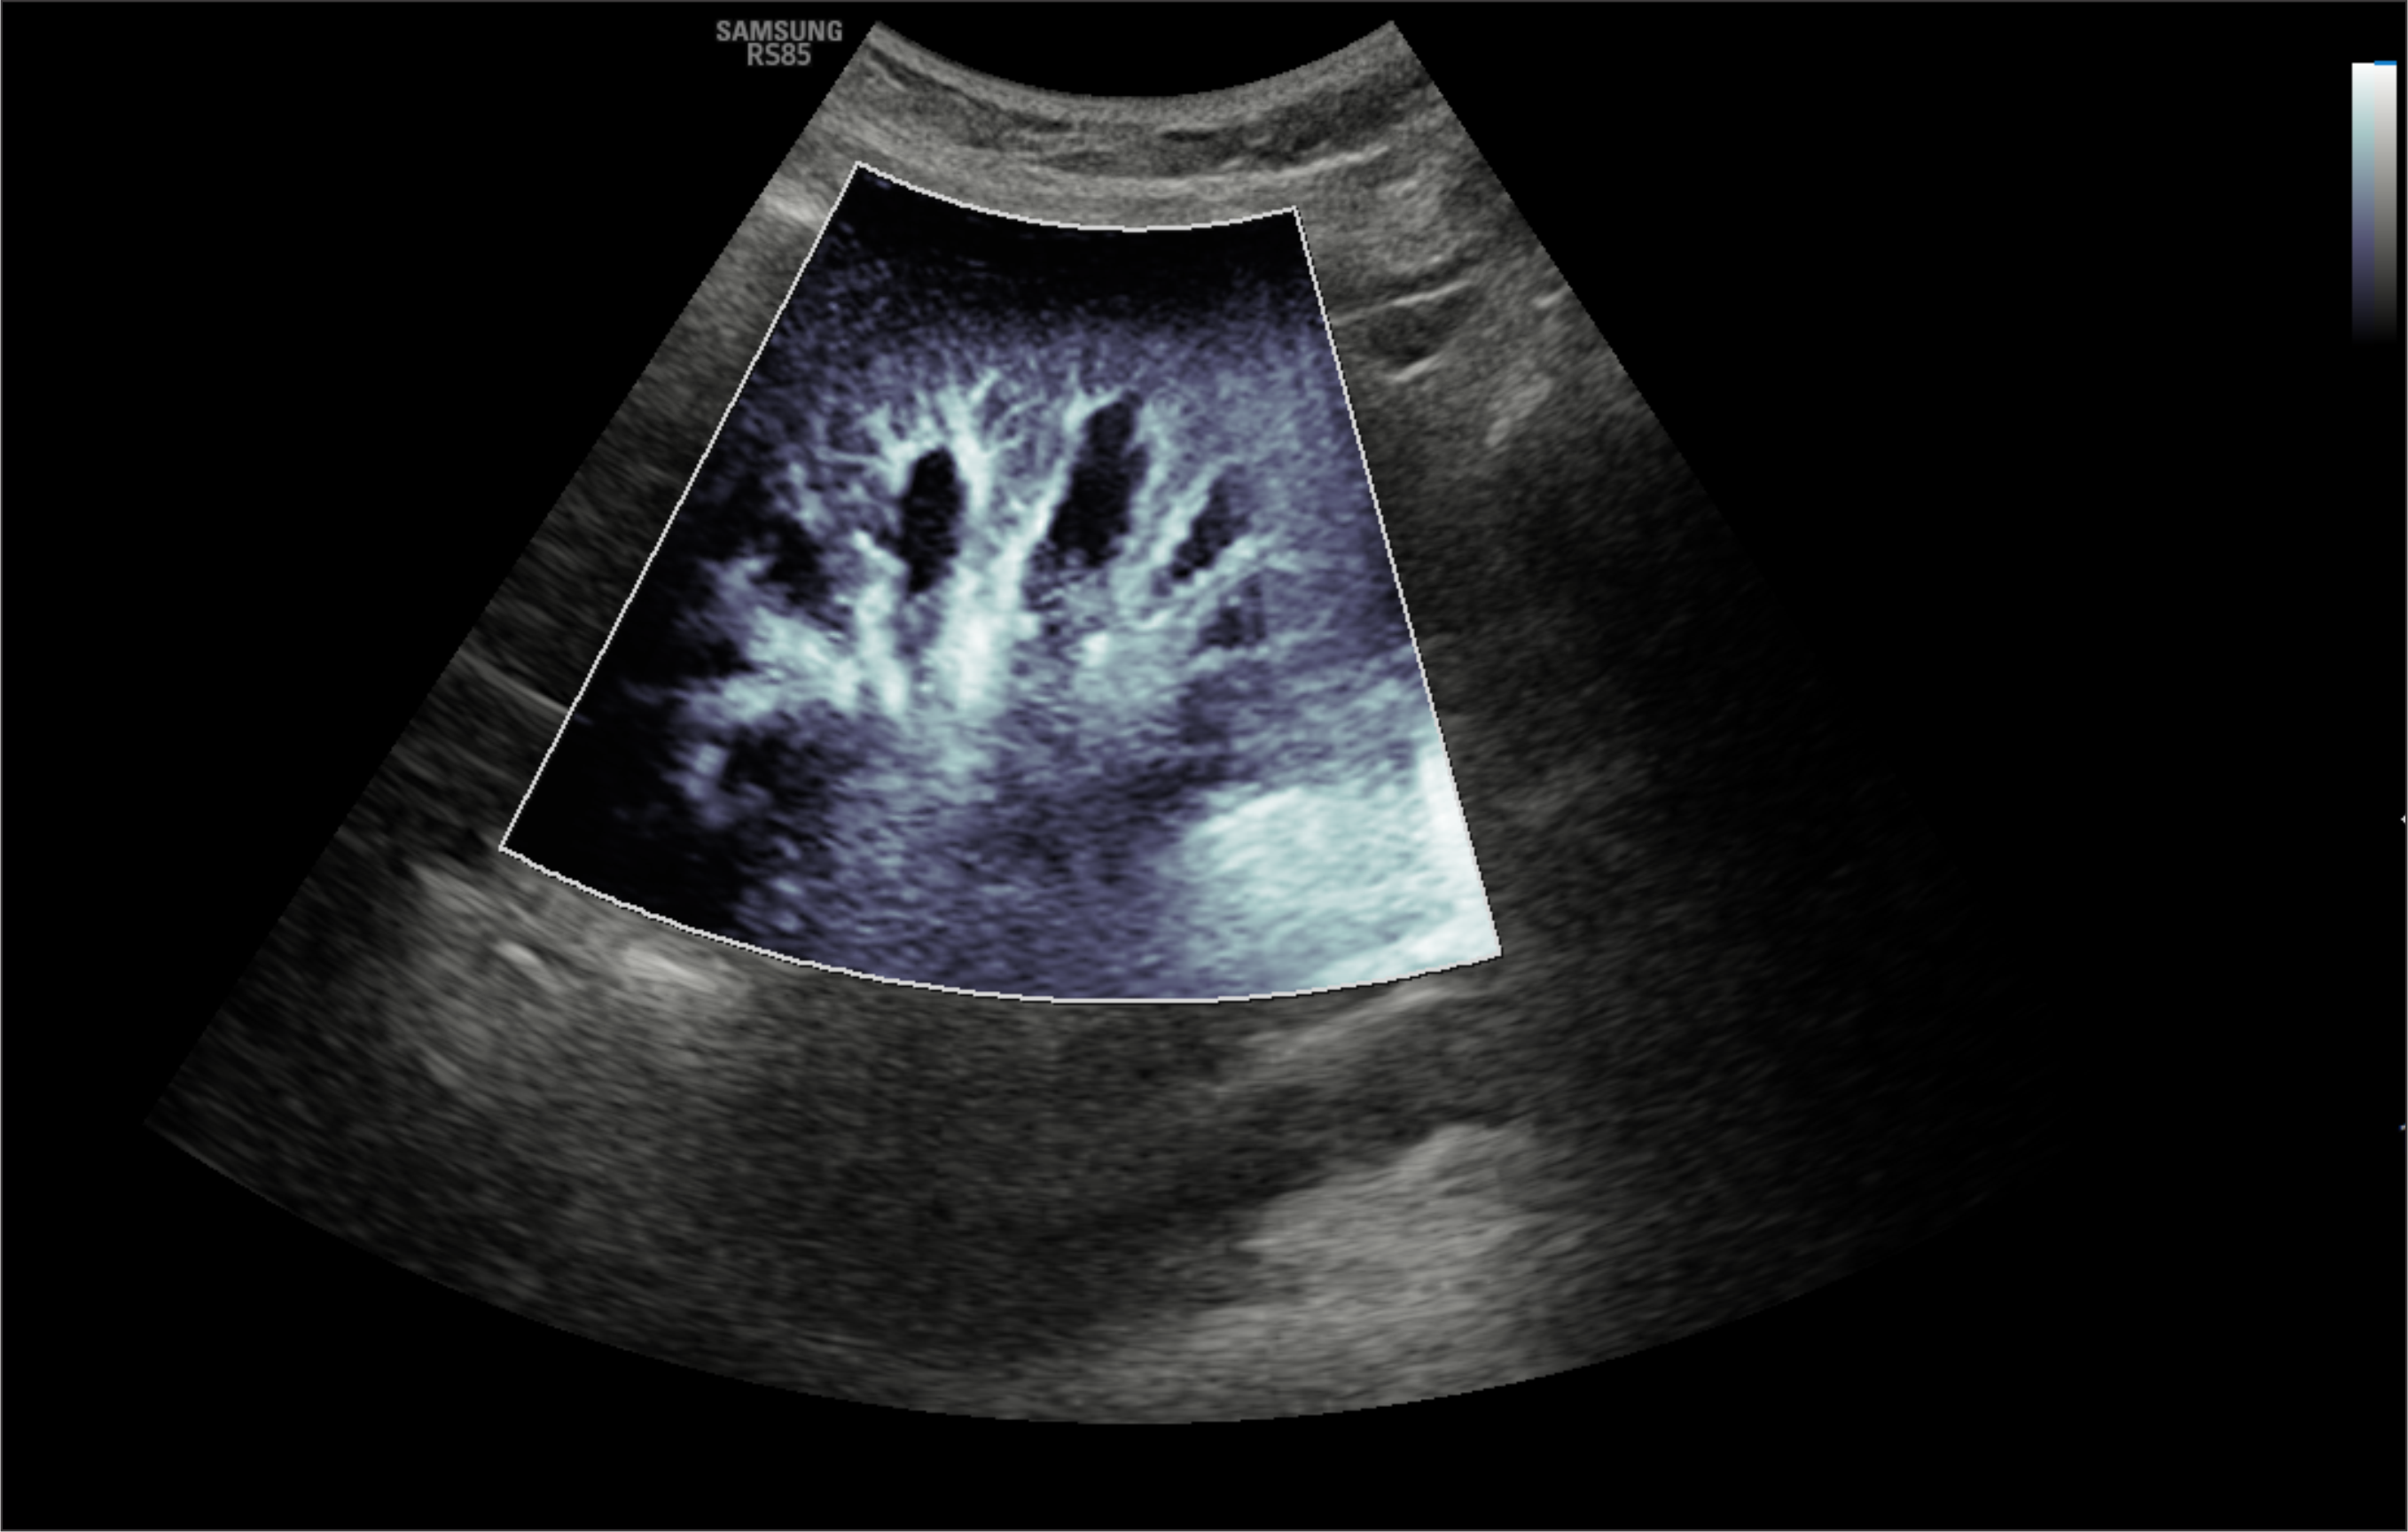

En Diagnoimagen incorporamos un enfoque de ecografía multiparamétrica, combinando modo B, Doppler color, Doppler de microflujo y elastografía, lo que nos permite una evaluación más completa y precisa en múltiples patologías.

🔹La ecografía Doppler permite evaluar el flujo sanguíneo en arterias y venas, siendo fundamental para el diagnóstico de insuficiencia venosa, várices, trombosis, estenosis carotídea y patología hepática.